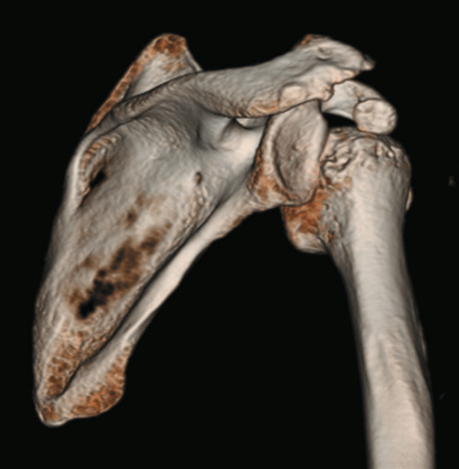

X線(レントゲン)検査

脱臼の方向を確認するほか、骨頭側(ヒル・サックス損傷)や関節窩側(骨性バンカート損傷)に骨の損傷がないかを評価します。反復性肩関節脱臼の診断には必須の検査です。